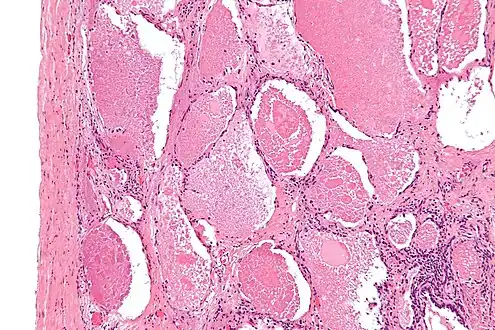

| Micrograph of pulmonary alveolar proteinosis, showing the characteristic airspace filling with focally dense globs referred to as chatter or dense bodies. H&E stain. | |

Intermediate magnification micrograph of pulmonary alveolar proteinosis. H&E stain.

Lung washings or tissue for histopathologic analysis are most commonly obtained using bronchoalveolar lavage and/or lung biopsy.[12] Characteristic biopsy findings show filling of the alveoli (and sometimes terminal bronchioles) with an amorphous eosinophilic material, which stains strongly positive on PAS stain and the PAS diastase stain. The surrounding alveoli and pulmonary interstitium remain relatively normal.[13] Electron microscopy of the sample, although not typically performed due to impracticality, shows lamellated bodies representing surfactant.[14] An alternative diagnosis with similar histomorphologic findings is Pneumocystis jirovicii pneumonia.[14]

Lung washings characteristically yield a fluid which is "milky"composition. Under the microscope, samples show 20-50 micrometer PAS-positive globules on a background of finely granular or amorphous PAS-positive material. There is typically a low numbers of macrophages and inflammatory cells (although this is variable).[13][14]